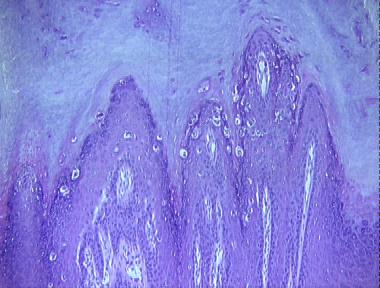

verruca plantaris

Histologic Features